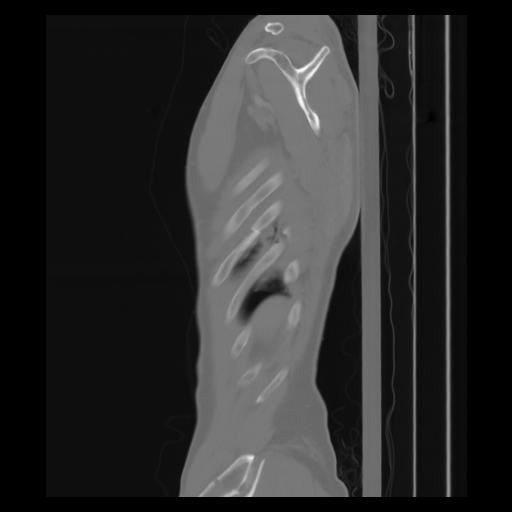

30 CUERPO,CE,Sagittal,3.000,CUERPO,Sagittal,